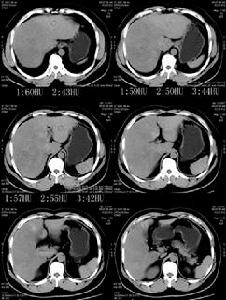

典型的腎病綜合徵臨床診斷並不困難,但由於老年人腎臟的老化改變以及其他系統性疾病可掩蓋某些腎病綜合徵的表現,使其變得不典型實際上做出準確的診斷的是不容易的因此為了明確腎病綜合徵的病因並確定適宜的治療方案許多學者認為有必要進行腎組織活檢,但因為腎臟老化改變有時必須結合臨床資料進行分析。

其它輔助檢查: 腎穿刺活組織檢查:該檢查可以為確定腎病綜合徵和病理類型提供形態學診斷並對治療方案確定的及估計預後有著指導性意義。